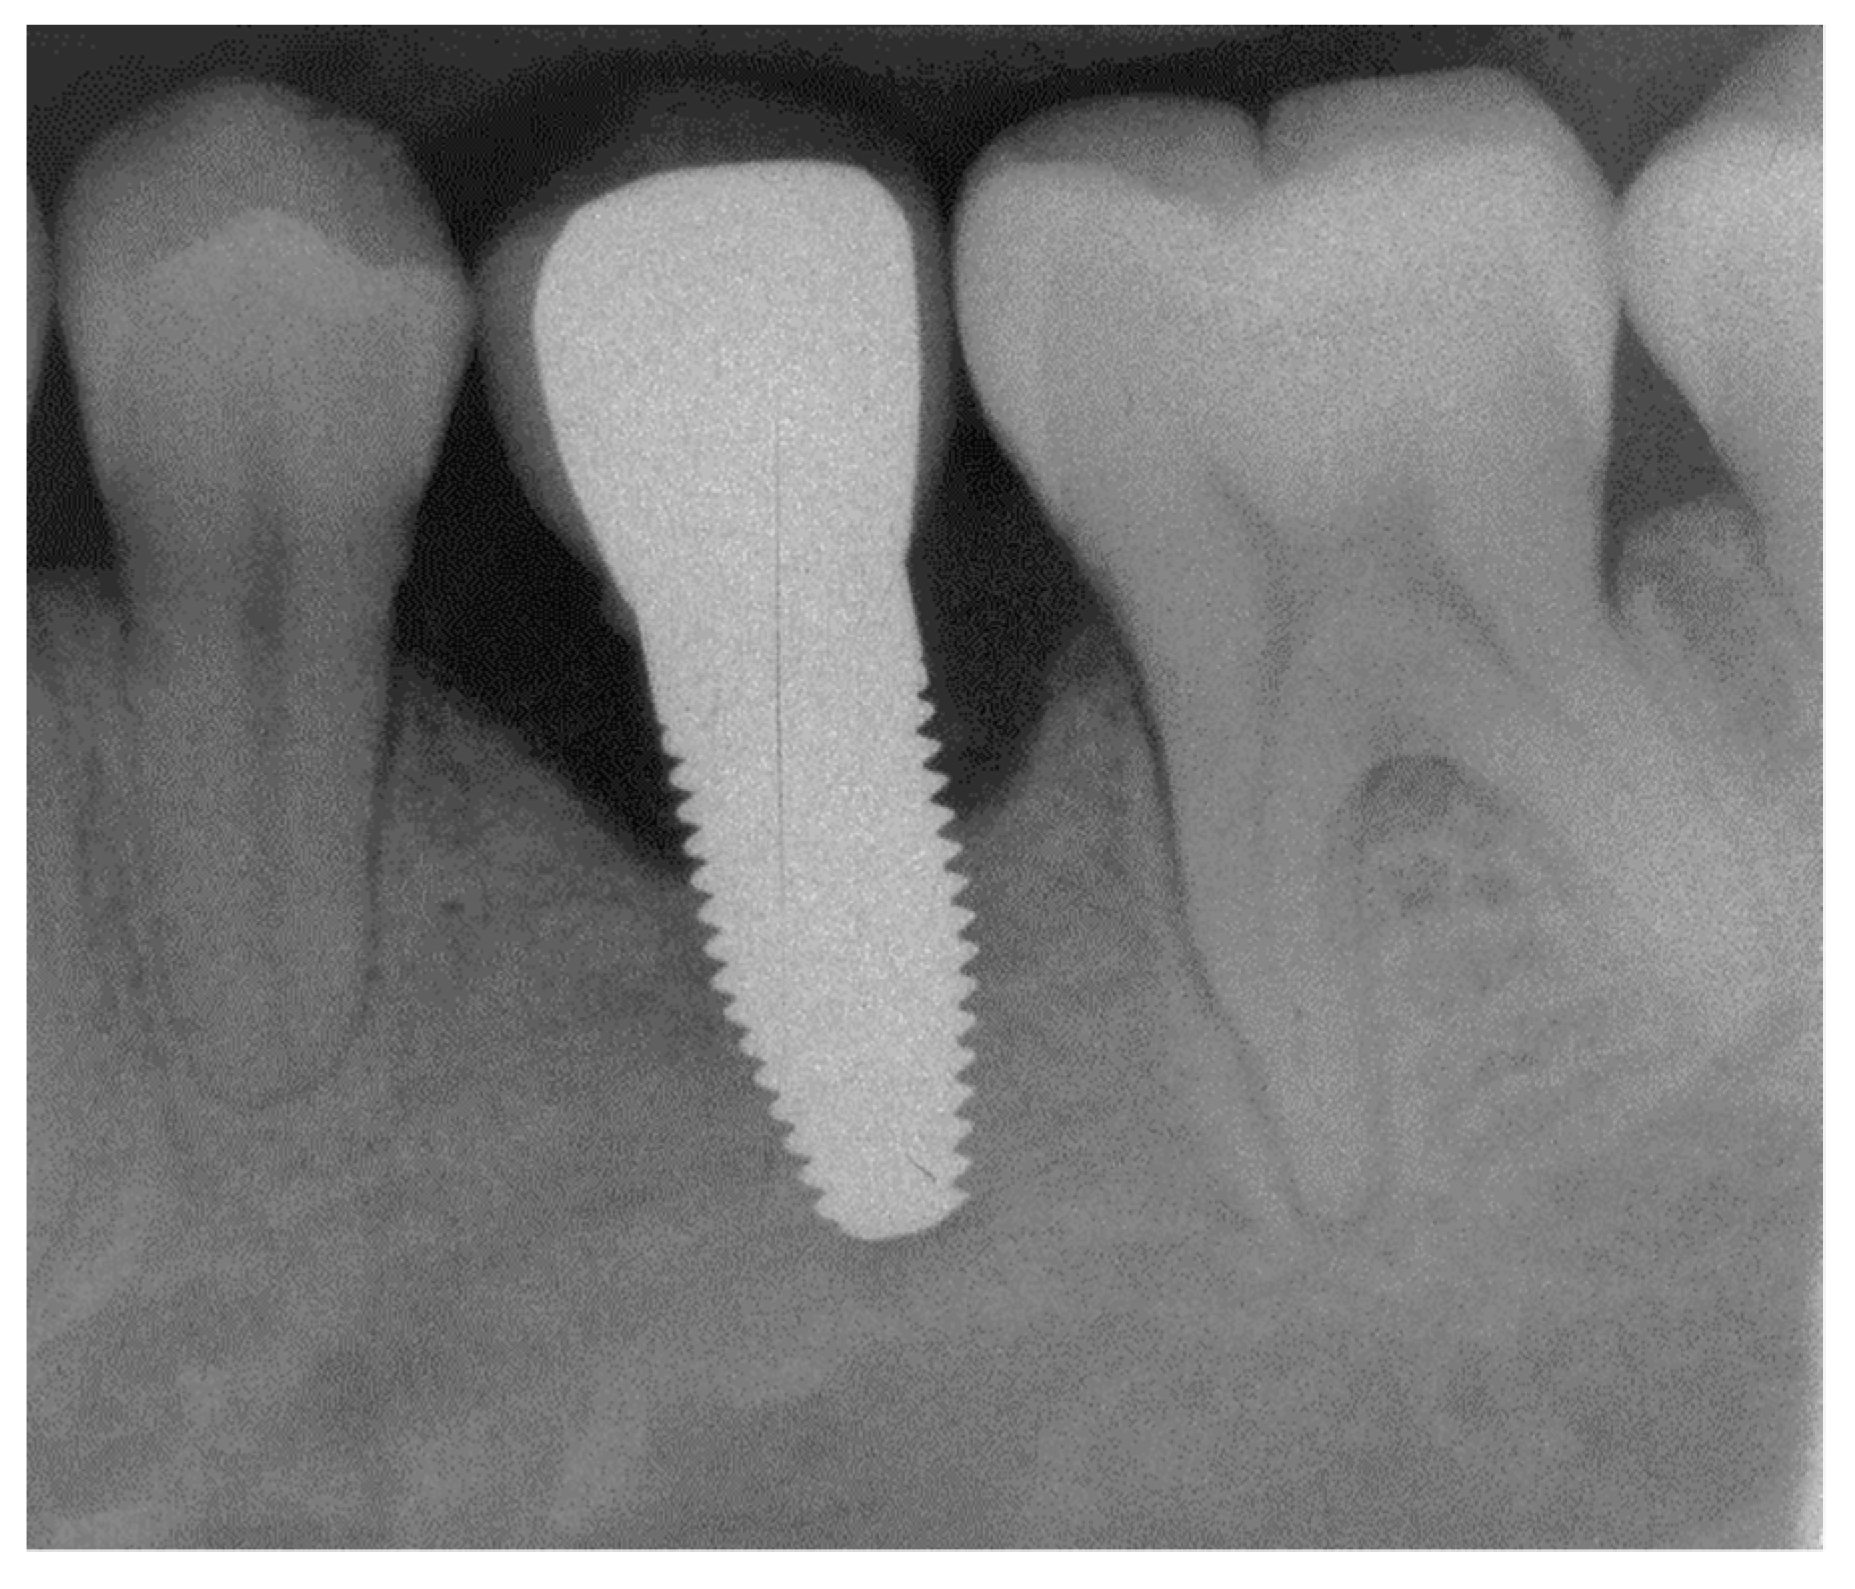

Figure A15.

Radiograph of the perimplant bone situation before crown cementation.

Figure A18.

Radiograph of the perimplant bone situation at the 1-year follow-up. The bone loss is already advanced. Therapy: conventional subgingival cleaning with ultrasound and plastic tips; rinsing with chlorhexidine, reinforcement personal oral hygiene.

Figure A21.

Radiograph of the perimplant bone situation at the 3-year follow-up. Compared to the 1-year follow-up, relatively stable bone situation.

Figure A24.

Radiograph of the perimplant bone situation at the 5-year follow-up. Aggravation of bone loss. Although, the clinical situation looks favorable, suppuration occurred. Patient requested removal of implant and no surgical intervention for cleaning.